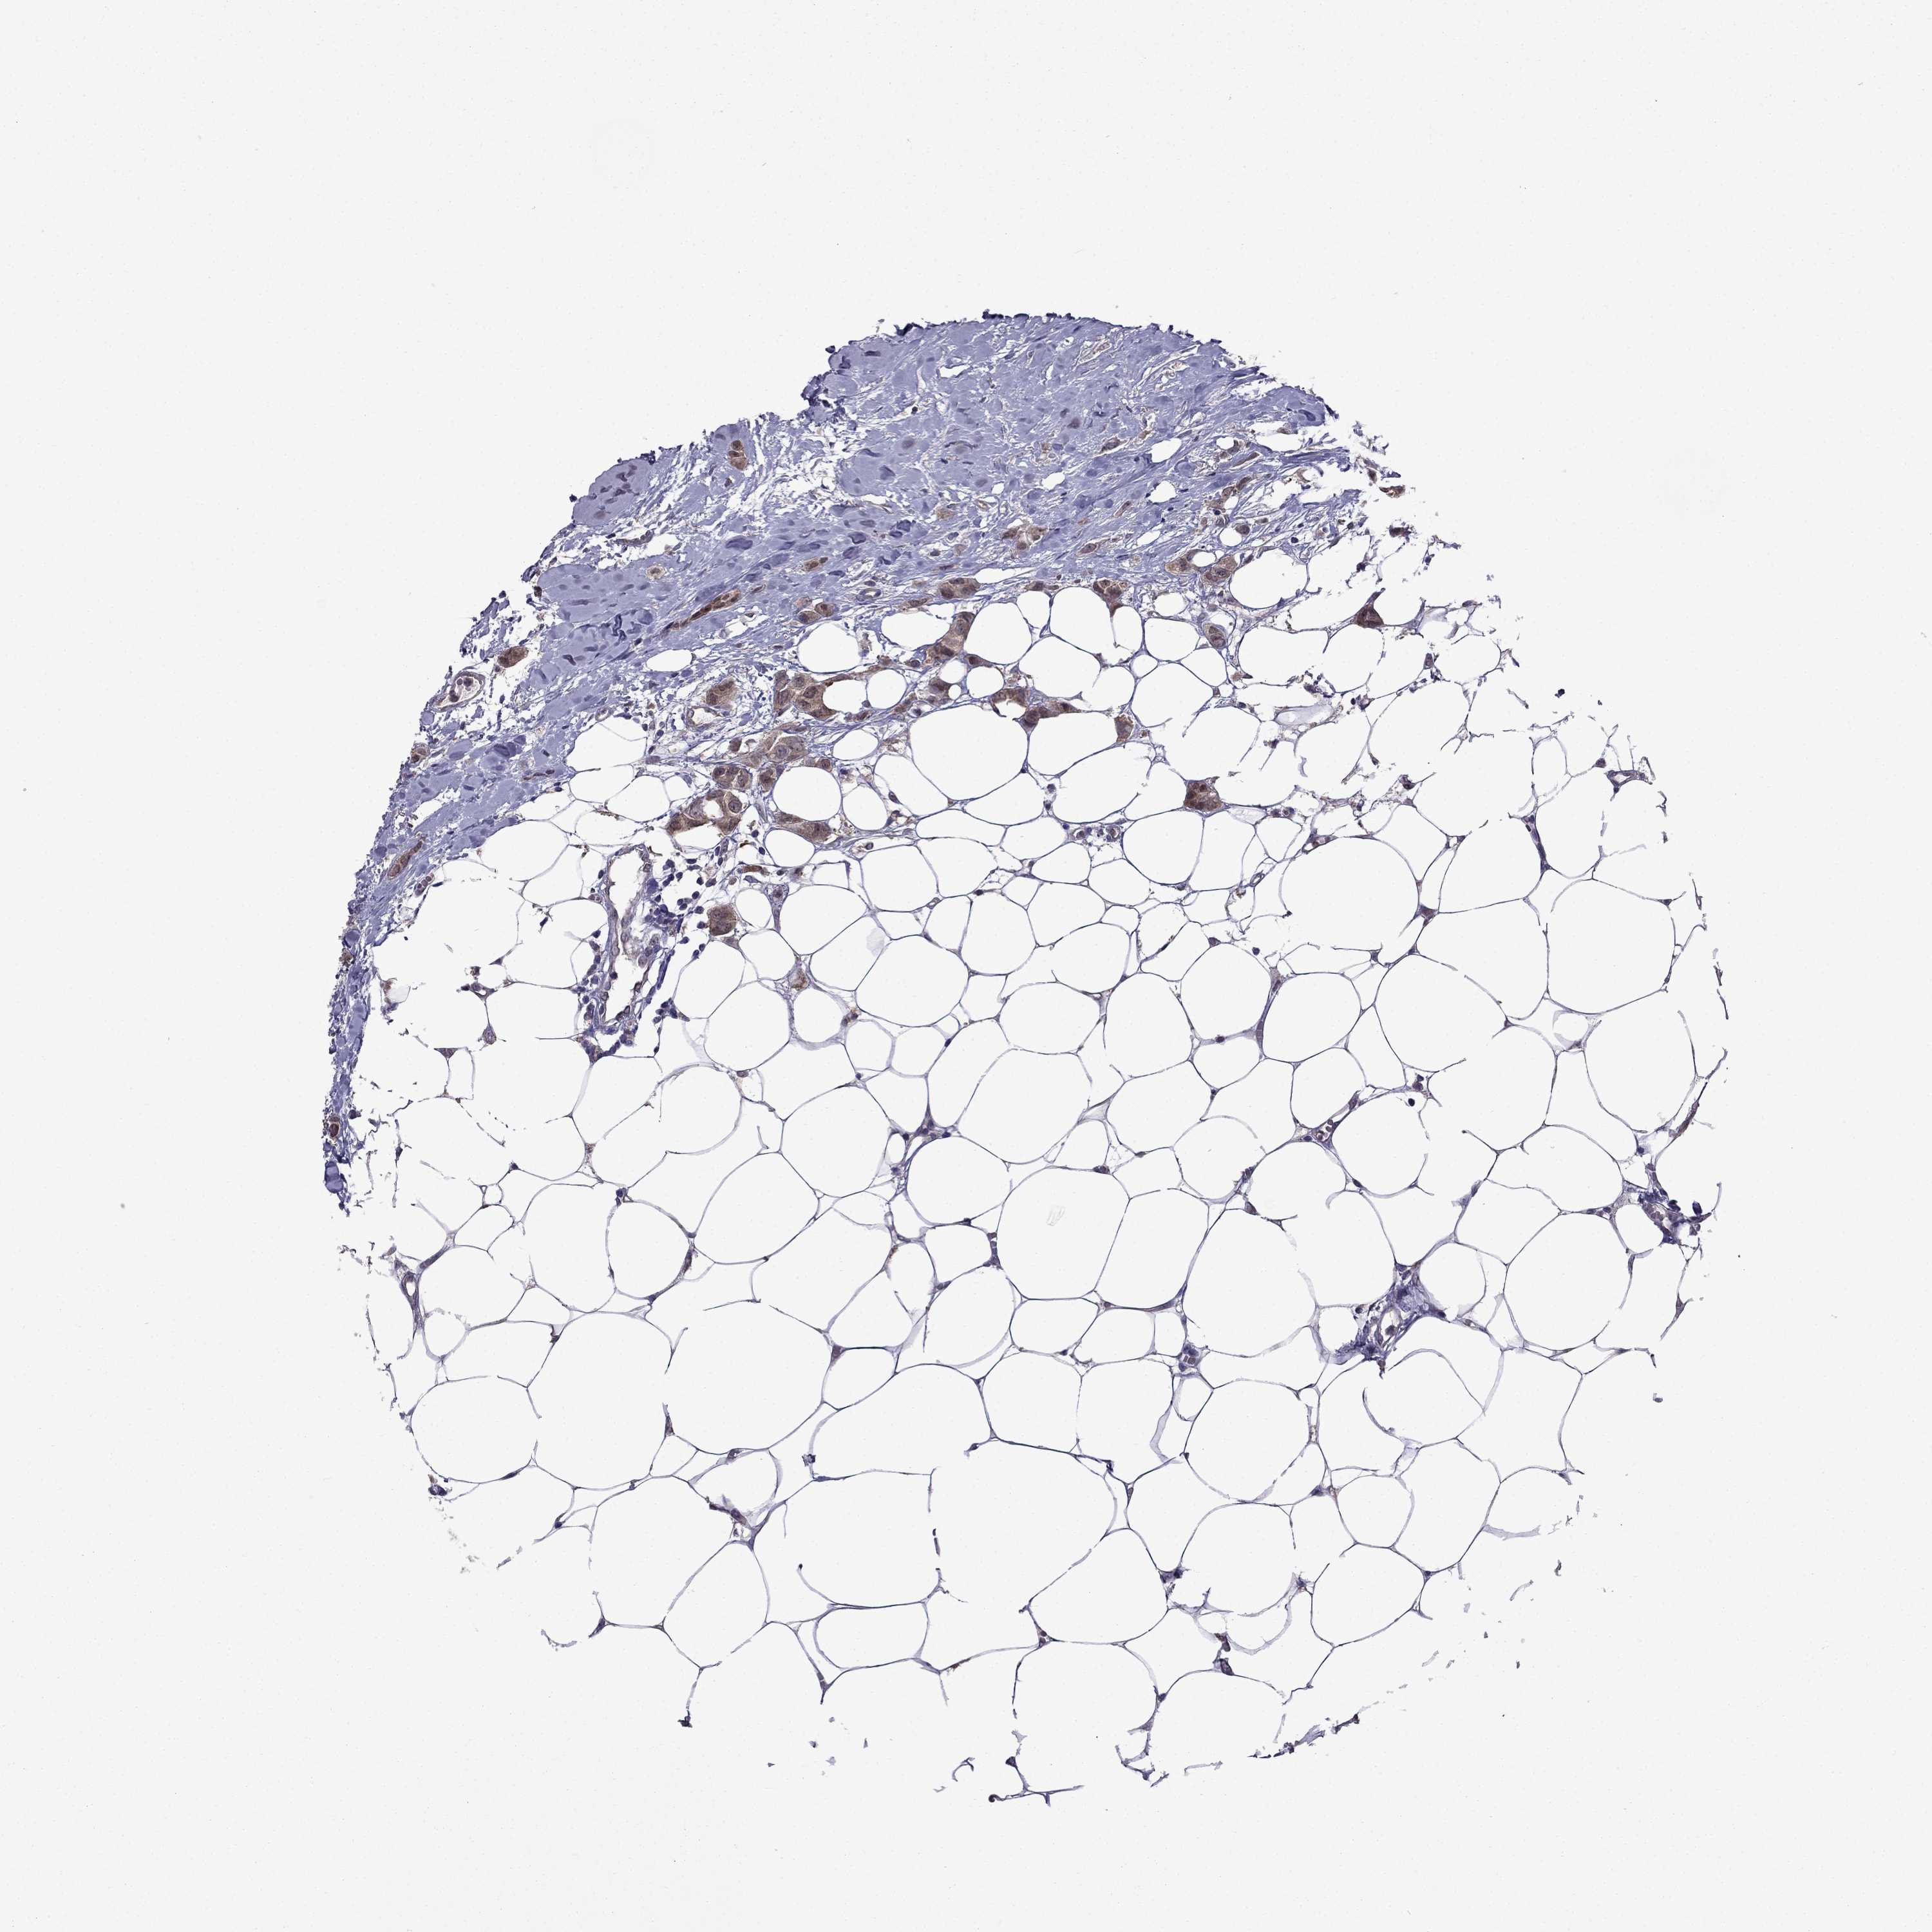

CANCER BREAST CANCER Show tissue menu

BRCA TCGA BRCA VALIDATION PROTEIN EXPRESSION